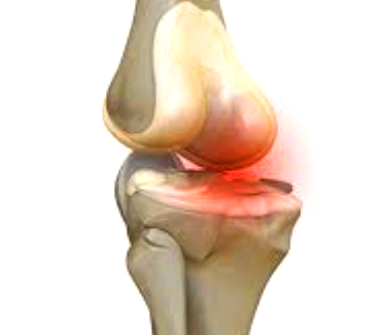

평소 조깅을 하거나 운동을 하면서 무릎에 체중을 싣게 되는데 이럴 때 통증이 지속되면 무릎 연골 손상을 의심해 볼 수 있습니다. 무릎 연골은 허벅지와 종아리뼈 표면을 덮고 있는 일종의 뼈를 보호하는 막으로 무릎 관절을 움직일 때 뼈가 서로 부딪혀 손상되는 것을 막아줍니다.

이런 연골도 나이가 들면 점차 닳으면서 뼈 표면이 노출되고 노출된 뼈는 여러 외부요인으로 자극이 되어 통증을 일으키는데 이것이 바로 퇴행성 관절염이라고 합니다.